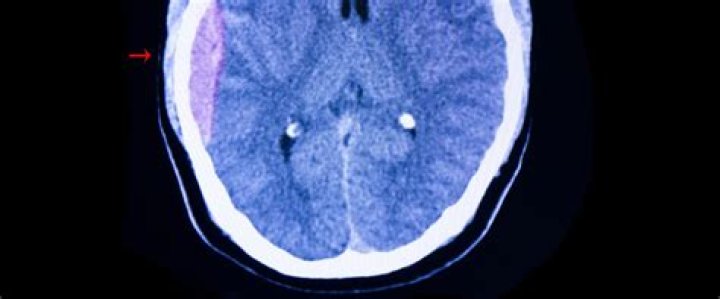

Complications. A severe head injury can result in pressure being placed on the brain because of bleeding, blood clots or a build-up of fluid. This can sometimes lead to brain damage, which can be temporary or permanent.

• Intracranial hematoma (ICH). This is bleeding under the skull in the brain that forms a clot. ...

Traumatic brain injury: pathology review